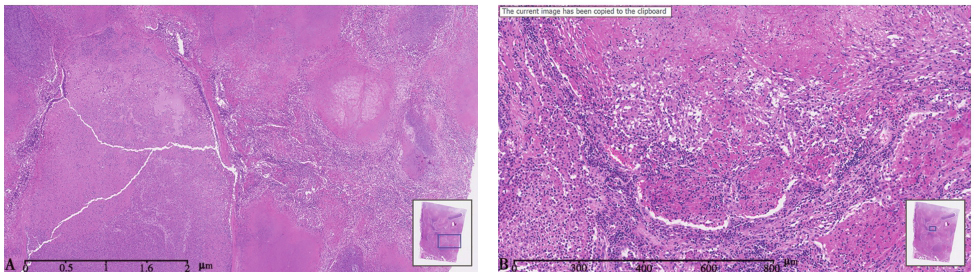

图8 肺脓肿胸部CT表现

女性患者,15岁,发热、咳嗽5天,出现进行性呼吸困难;发病8天后出现多发肺脓肿,伴双侧胸腔积液(佘丹阳教授提供)